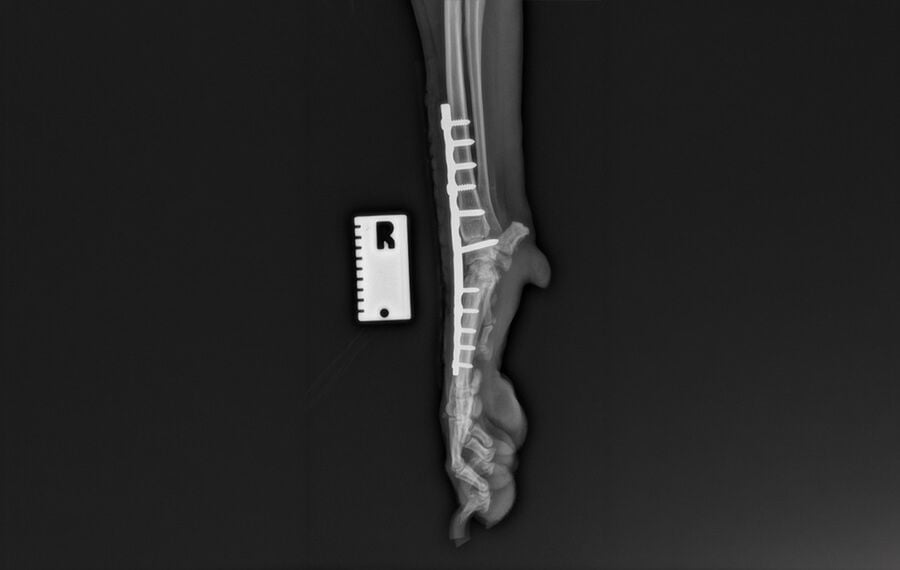

Pancarpal Arthrodesis (fusion of the wrist)

This is the complete fusion of the carpus (the joint between the paw and the elbow). Despite the joint being fused solid, overall limb function usually remains excellent. This is because the shoulder and elbow joints compensate for the lack of movement at the wrist.

- Appearance: To the untrained eye, a dog or cat with a fused carpus will often walk and run normally.

- Common Indications: Most frequently performed for hyperextension injuries (common in active dogs who land awkwardly) and complex fractures of the carpal bones.